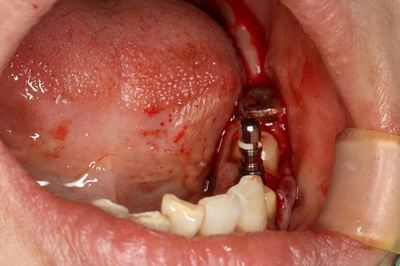

インプラントの埋入を終えました。

インプラントフィクスチャーの上部です。

カバースクリュー高さ0.5mmで封鎖します。

カバースクリューで封鎖しました。